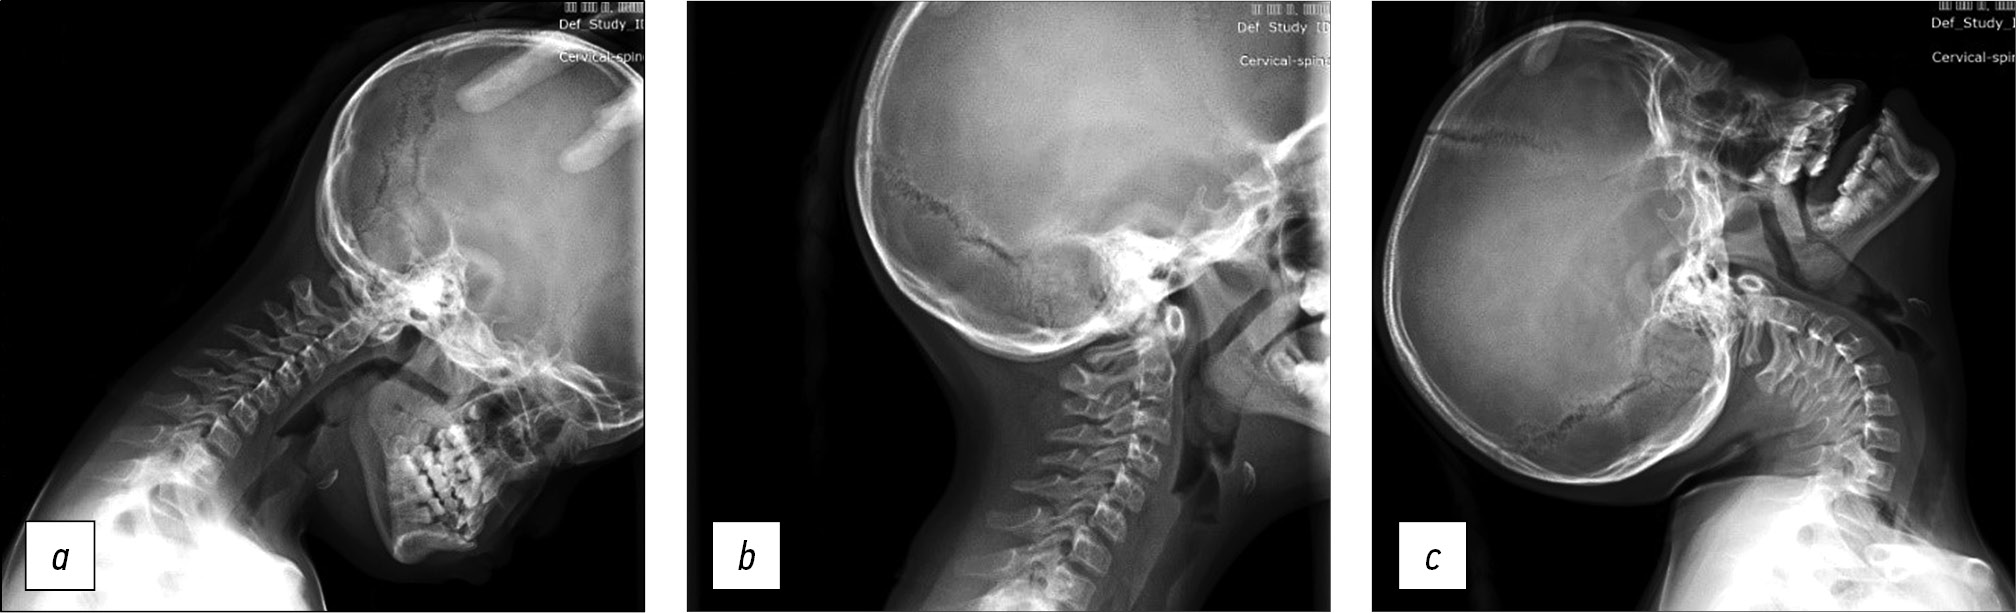

A 14-year-old female teen was admitted for a cervical spine screening examination in individuals with Down syndrome. She complained of progressive weakness in the upper and lower extremities and forced head position with rotation to the right for the past 3 months. Results of the CT and MRI of the cervical spine led to the following diagnosis: Down syndrome, rotational atlantoaxial blockage, left-sided chronic transligamentous subluxation of the C1 vertebra with spinal canal stenosis (Fielding–Hawkins type II), cervical myelopathy, and deep tetraparesis (Frankel C) (Fig. 2).

Fig. 2. Instrumental methods of examination: a — MRI picture of transligamentous subluxation with spinal canal stenosis and myelopathy at the level of C1-C2, b — 3D CT reconstruction, c — CT scan of the cervical spine, sagittal slice with visualization of disturbed craniovertebral relations. MRI — magnetic resonance imaging, CT — computed tomography.

CT revealed gross violations of craniovertebral relationships: the Cruveilhier joint gap (atlantodental interval [ADI]) was 1.06 cm, and the space available for the spinal cord at the C1 level (SAC C1) was 5.17 mm. These changes indicate gross stenosis of the spinal canal. A bone block developed in the left lateral atlantoaxial joint (Fig. 3)